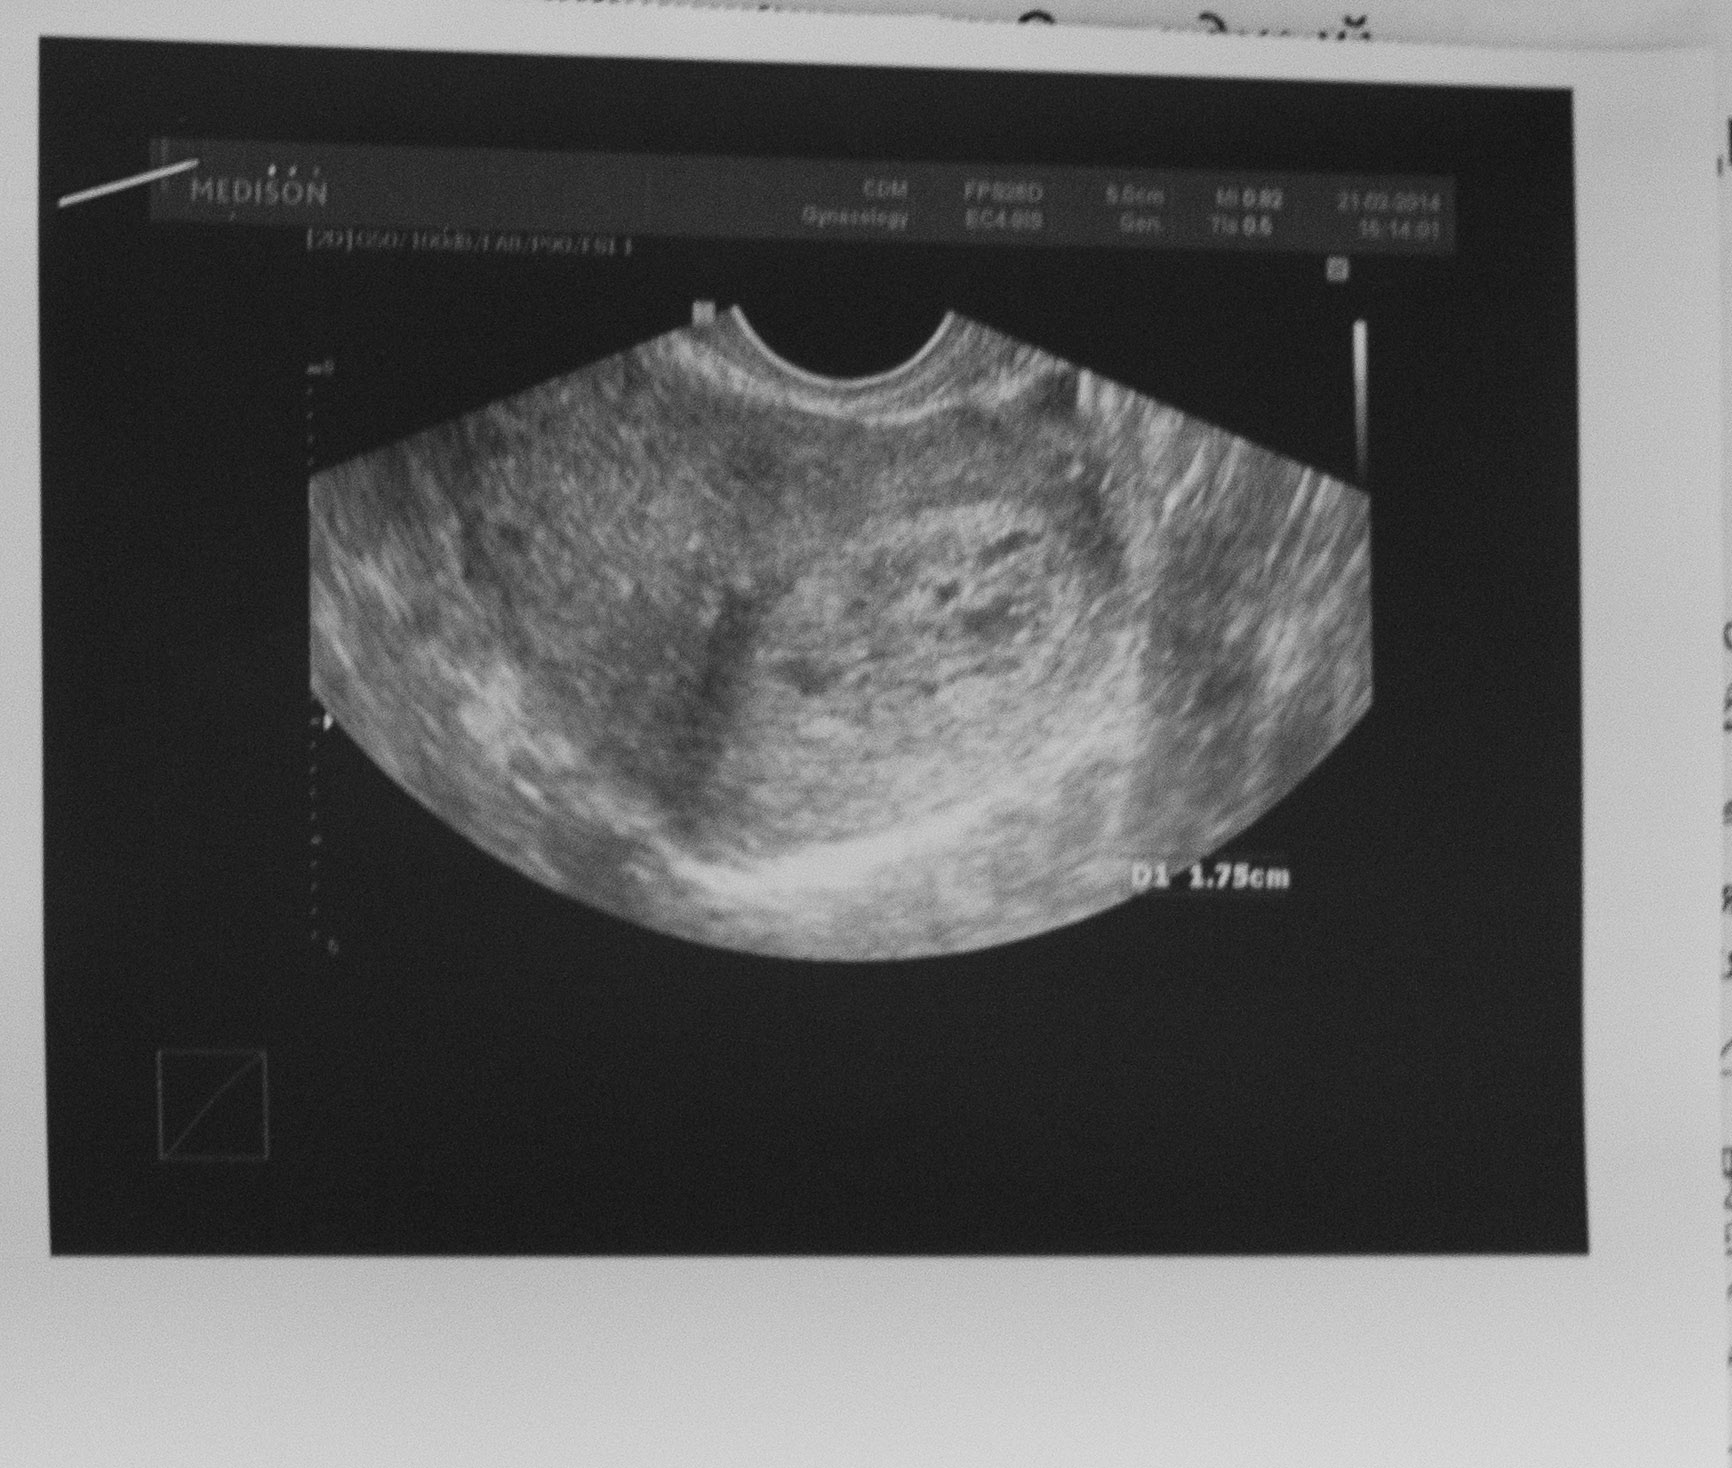

Медицина и диагностика: Инвазивный пузырный занос на УЗИ

Раздел: Альбом идей